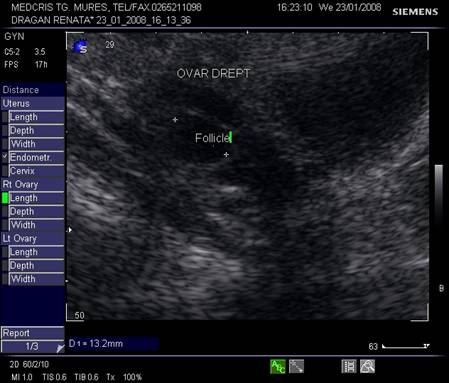

Dupa ziua a 5-7, un folicul ovarian devine dominant , fata de ceilalti ce devin atretici. In ziua 10 -a - 11-a foliculul depaseste 12 mm diametru. Cresterea foliculara de 2 - 3 mm/zi ne duce la un folicul preovulator de cca 21 mm diametru (24 - 26 mm). Doi foliculi dominanti au fost identificati in 10% din ciclurile spontane [8].

Deoarece foliculii sunt ovoidali, diametrul mediu conteaza pentru foliculometria, dupa masurarea a 3 diametre si impartirea la 3.[6]

Fig. nr.371. Folicul selectat ziua a XI a de ciclu menstrual, la ecografia transvaginala